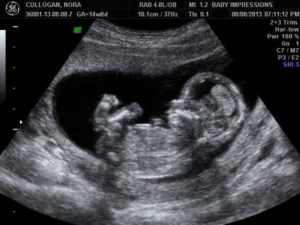

Фото снимок плода на 11 неделе

УЗИ на 11-й неделе беременности.Скрининг 11 недельУЗИ на 11-й неделе беременности.Скрининг 11 недель

К моменту первого посещения УЗИ рост ребенка, вернее, копчико-теменной размер, равен 4-5 сантиметрам. У ребенка сформировались уже необходимые органы, их можно рассмотреть на экране монитора. Правда, ручки и ножки у него еще непропорционально сложены. А ручки даже длиннее ножек, зато они уже хватают вокруг. Малютка уже активен.

Есть уже и камеры в сердечке. Пульс ударов 120-160 в минуту. Но еще нет различий между венозным и артериальным потоками.

Продолжается развитие ЖКТ, половых органов. Формируются печень, почки. Ребеночек уже заглатывает небольшое количество воды. Это сигнализирует о нормализации процесса дыхания.

Поскольку кожица у малютки пока тонкая, сквозь нее просвечивают не только все органы, а и сосудики. Можно просмотреть спинной и головной мозг.

К одиннадцатой неделе плацента, как правило, еще не сформировалась, а ее «начало» называется «хорион». Он чаще всего располагается на задней или передней стеночке плодного пузыря. Неправильным считается расположение хориона ближе, чем на 5 мм от зева матки. Недопустимо и перекрытие харионом зева. Степень зрелости этого органа должна равняться нулю.